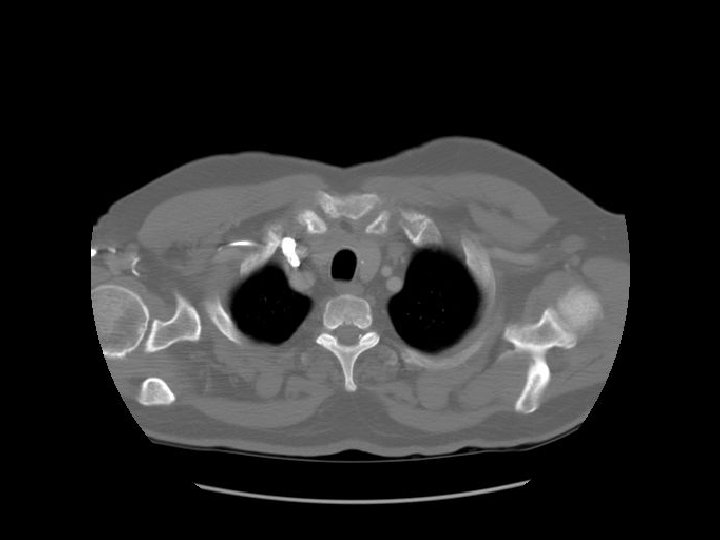

Humerus Cervical spine Clavicle Scapula

Pectoralis major AC joint Supraspinatus